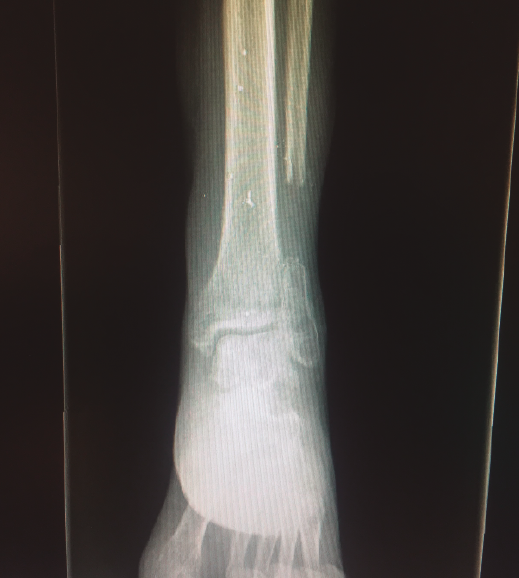

Figura 4. Radiografía tomada 5 meses después, tras el tratamiento conservador.

La fractura del peroné se trató de forma conservadora (Figura 4).